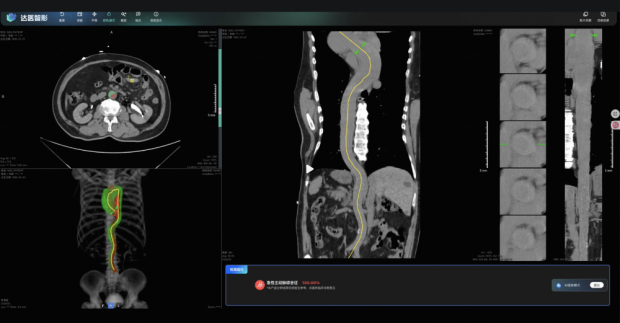

為此,達摩院開發了一套系統,和醫院的影像歸檔系統即時連接。當CT掃描結束,算法在後台數秒鐘就完成讀片,如果是高風險的AAS患者,AI會即時“紅色彈框”給醫生。

醫生點進去,不止能看到AI給出的AAS概率值,更重要的是,AI重建了血管三維圖像,勾畫出主動脈外壁和真腔,並且點出懷疑的病灶位置在哪裏。

根據前瞻性多中心研究結果,14436例平掃CT中共有14個AAS相關陽性結果,對照組放射科醫生初篩診斷出3個,而經過iAorta輔助的醫生,檢出數提升到11個,靈敏度從21%提高到79%。

在上海一家試點三甲醫院胸痛中心,兩個月內,iAorta模型輔助醫生,從15584人中精準找出21例AAS患者(總計包含22名),敏感性和特異性分別達到95.5%和99.4%。

而且,這21名AAS患者確診的時間僅有102分鐘,也就是從入院算起,到最終CTA結果出來確診,只要1.7小時。而文獻顯示,A型主動脈夾層此前的中位確診時間是4.3小時。